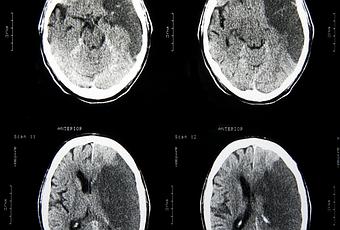

D’après une étude britannique, les accidents vasculaires cérébraux (AVC) touchent de plus en plus de personnes âgés de moins de 60 ans dans le monde. Ce sont surtout les pays en voie de développement (PVD) qui sont concernés.

En 2010, d’après les données analysées pour cette étude, pratiquement 17 millions d’accidents vasculaires cérébraux se sont produits dans le monde en 2010, soit 68% de plus qu’en 1990. Mais si ce taux de mortalité a baissé en 20 ans de 37% dans les pays développés, il a augmenté de plus de 40% dans les PVD. Au total, les AVC ont provoqué la mort de presque 6 millions d’individus en 2010. En France, ce chiffre est de 150 000.